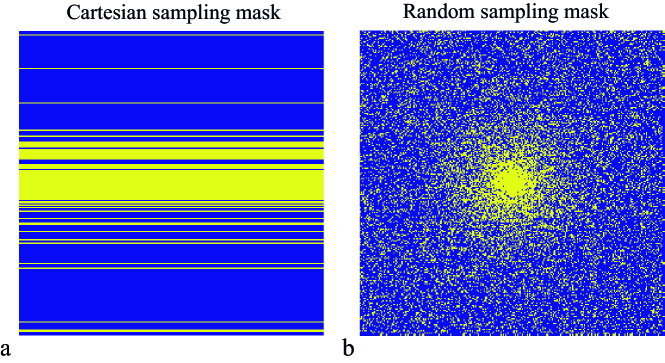

Undersampling

Two undersampling schemes are studied: a random line pattern with variable density in the foot-head direction and a fully random pattern with variable density, as shown in Fig. 2. Undersampling factors of four (R=4) and eight (R=8) were studied.